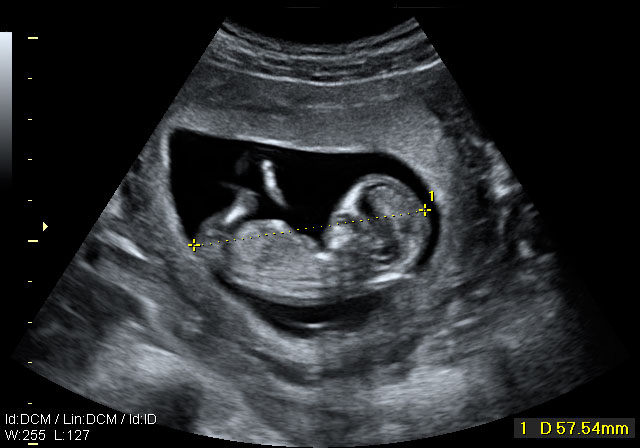

Ecografía Embarazo 2D y 3D - SEMANA 12